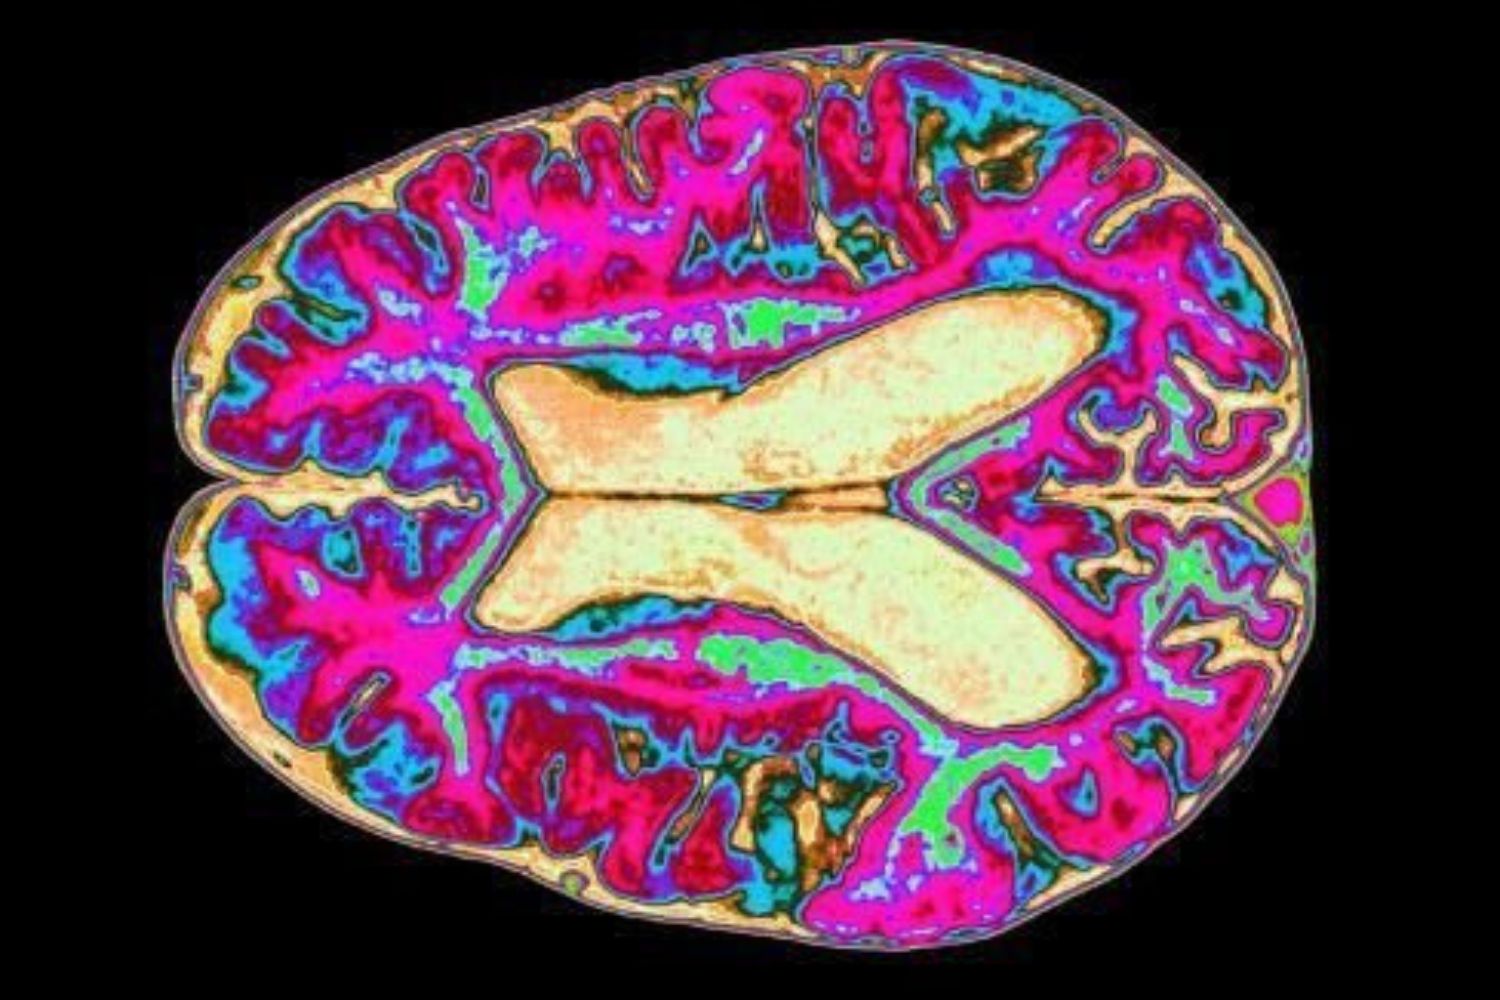

Grande parte dessas ideias está ligada à chamada teoria do processamento preditivo. Segundo esse modelo, o cérebro funciona como um sistema que cria previsões constantes sobre o mundo, combinando experiências passadas e informações sensoriais. O objetivo é reduzir a incerteza — embora eliminá-la completamente seja impossível.

O filósofo cognitivo Mark Miller, pesquisador da Universidade de Toronto e da Universidade Monash, argumenta que esse equilíbrio imperfeito é justamente o que mantém o cérebro saudável. Para ele, a mente prospera quando alterna entre previsibilidade e surpresa, revisando seus modelos internos diante de novas informações.